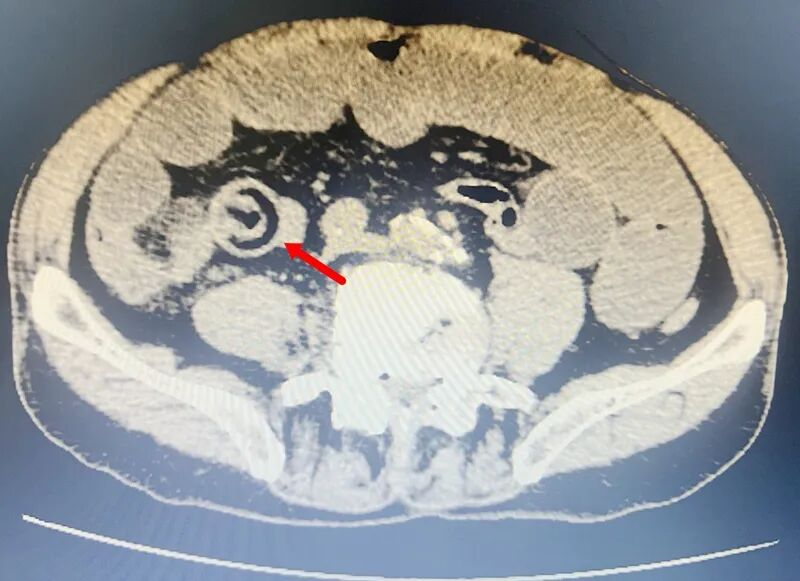

▲患者术前上腹部CT片

欧爷爷的情况就是典型的“异物梗阻”:整颗香菇没有被充分咀嚼,质地偏硬且不易消化,在小肠的狭窄部位“卡壳”。一开始他只是觉得肚子胀、隐隐作痛,以为是消化不良,直到后来腹痛加剧、呕吐不止,家人赶紧送医,检查后才发现是小肠完全梗阻,必须立刻手术。